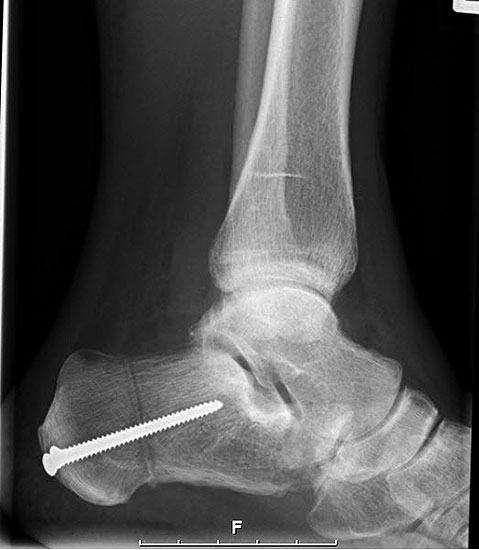

Im Stadium III der Tibialis posterior Sehneninsuffizienz bei fixierter Deformität und/oder erheblich eingeschränkter Inversion im USG aber stabilen und flexiblen Chopart-Gelenk und weniger als 10° fixierter Vorfußsupination eine in-situ oder leicht korrigierende USG-Arthrodese indiziert. Der Vorteil einer isolierten USG-Arthrodese gegenüber einer Triple- oder Double-Arthrodese ist die verbleibende, funktionell wichtige Beweglichkeit in der Chopart-Gelenkreihe. Um einem persistierenden fibulocalcanearem Impingement sicher vorzubeugen, sollte die USG-Arthrodese in maximal 5° Valgus- oder sogar Neutralposition erfolgen. Zur Prophylaxe eines Rezidivs wird die USG-Arthrodese zudem häufig mit einer medialisierende Tuber calcanei Osteotomie und / oder einem FDL-Transfer kombiniert (Abb. 12).